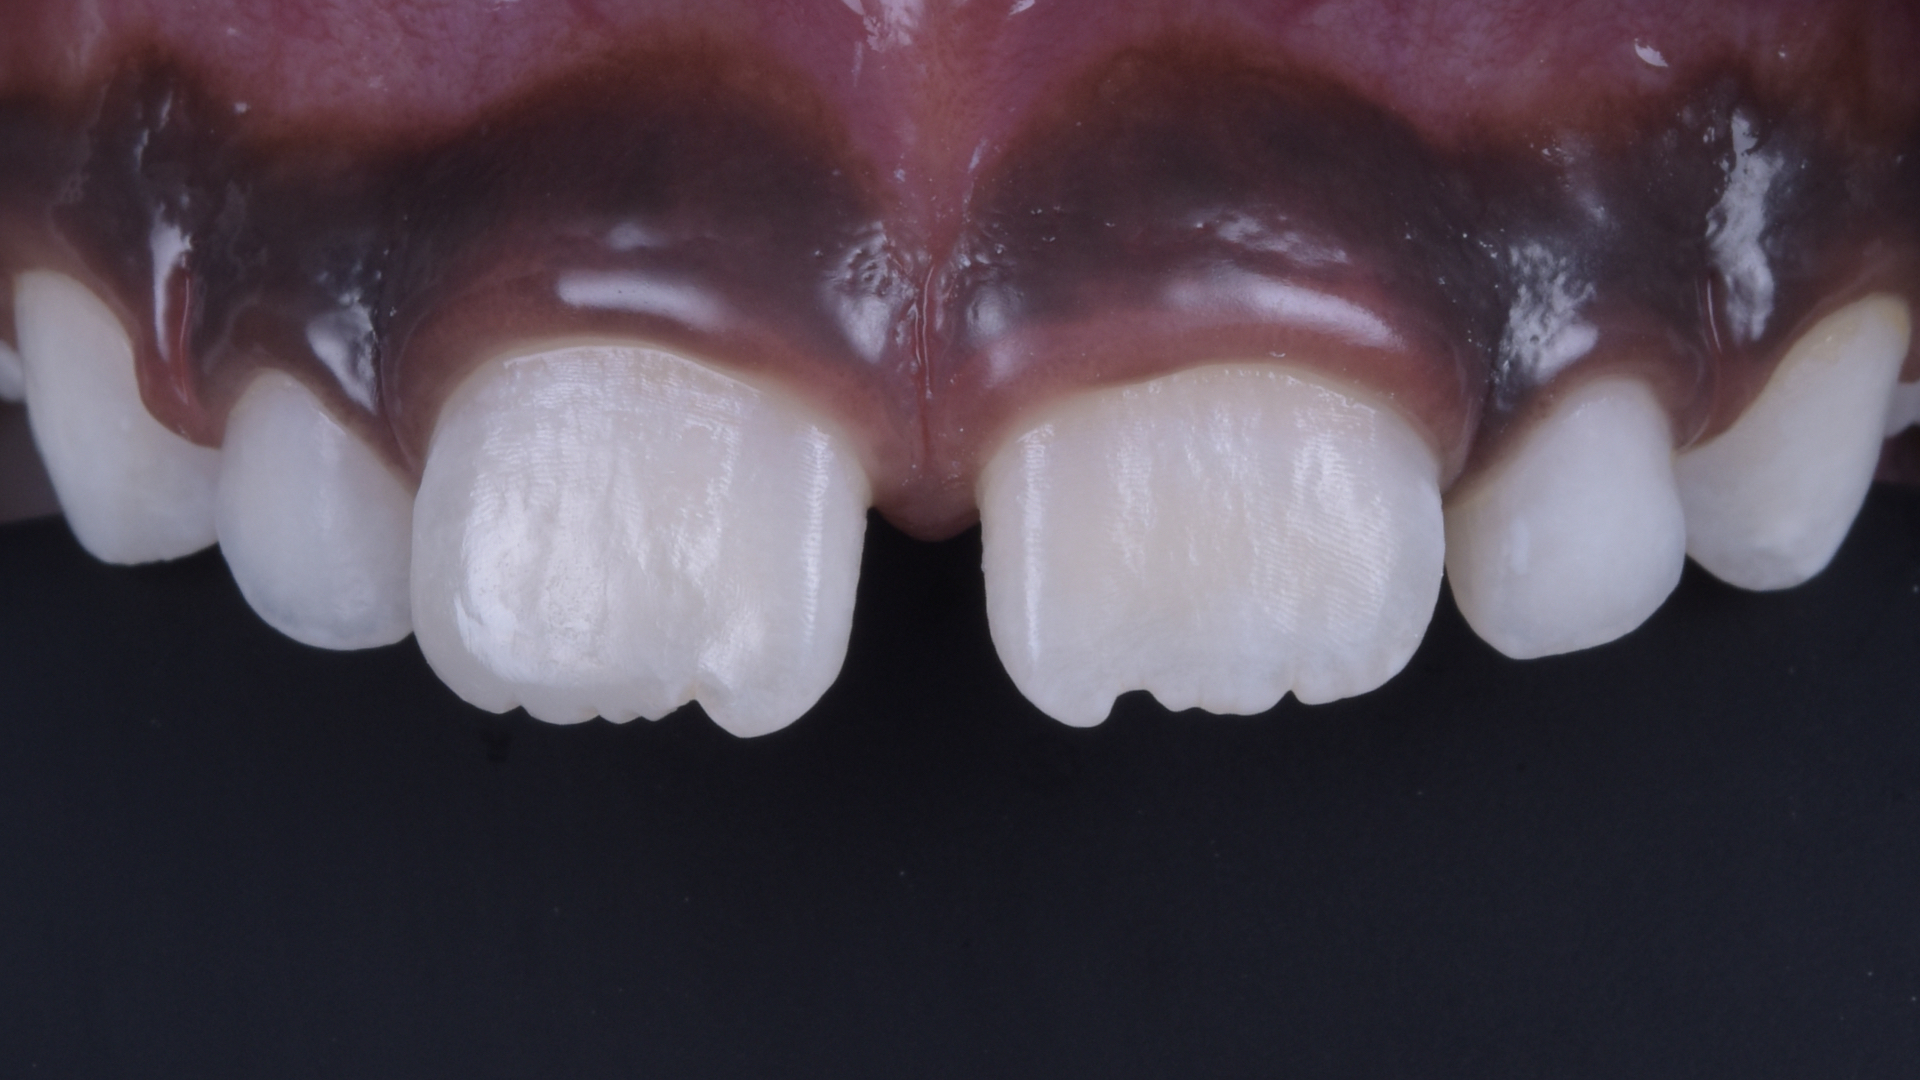

Ausgangssituation

Detailansicht der Oberkiefer-Frontzähne. Horizontale Kronenfraktur unter Einbeziehung der Inzisalkante sowie des distalen Anteils von Zahn 11.